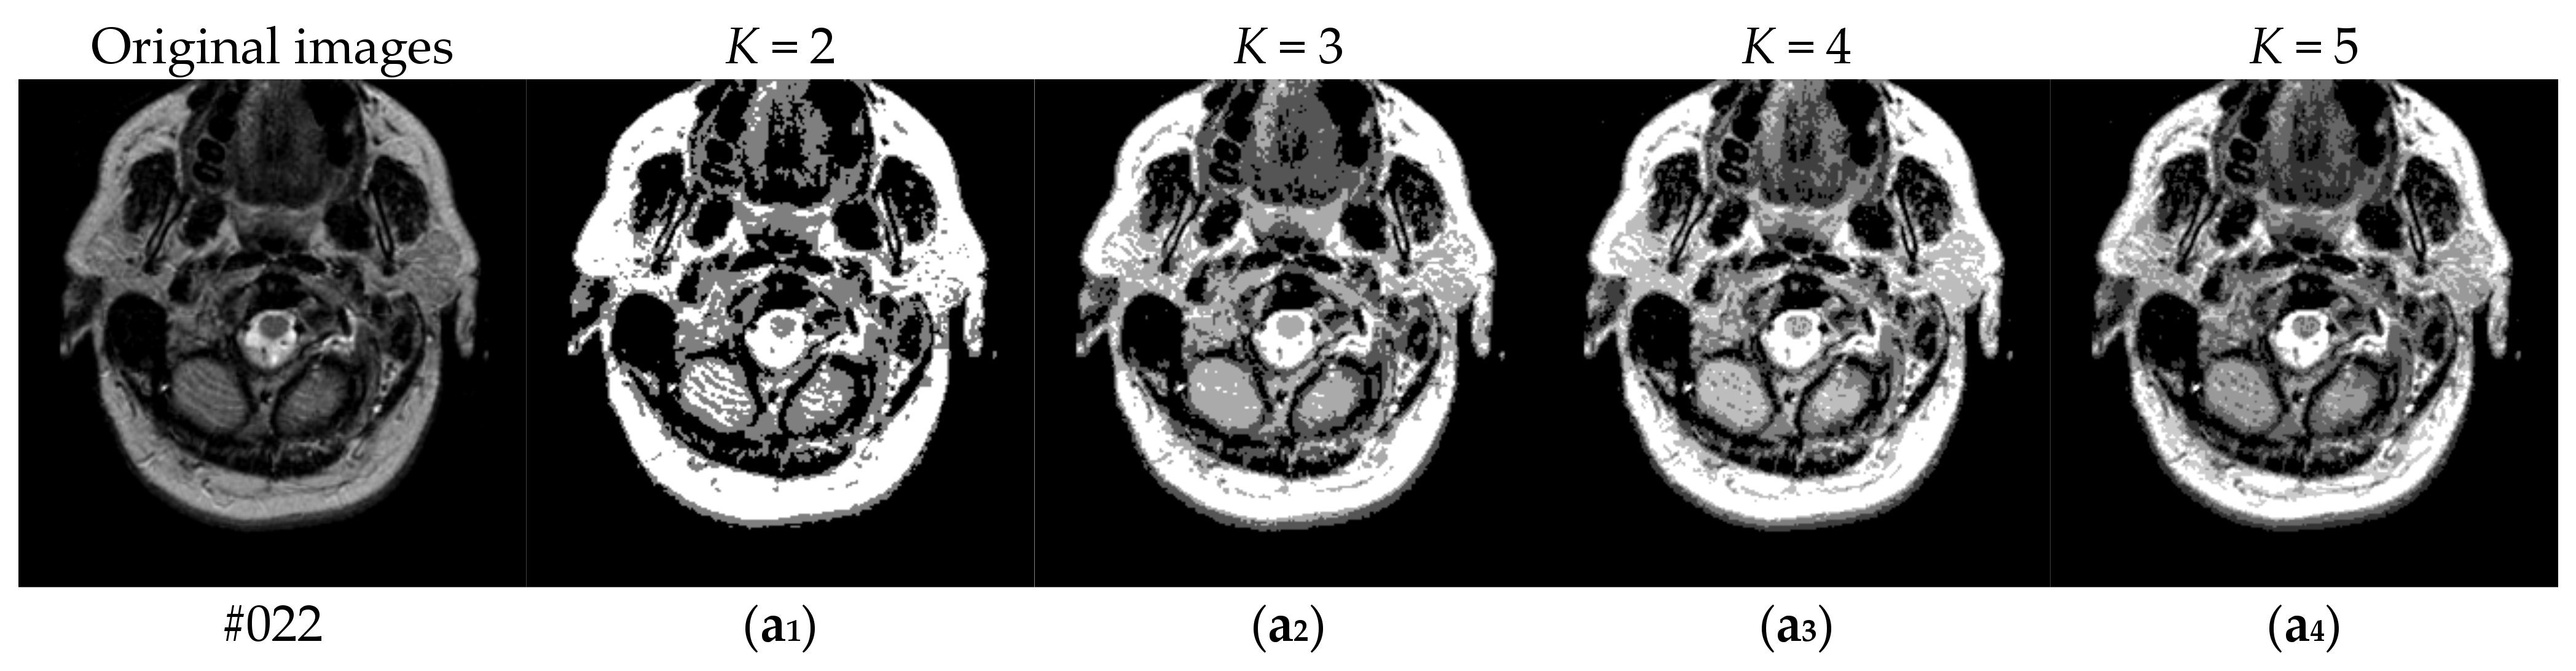

To verify the performance of the proposed algorithm, five representative multi-threshold segmentation algorithms are selected for comparative experiments. The five comparative experimental algorithms are: (1) image threshold segmentation algorithm based on particle swarm optimization (PSO), (2) image threshold segmentation algorithm based on bacterial foraging (BF), (3) image threshold segmentation algorithm based on adaptive bacterial foraging (ABF), (4) image threshold segmentation algorithm based on Nelder-Mead simplex (NMS), (5) image multi-threshold segmentation algorithm based on real coded genetic algorithm (RCGA) [43]. The number of thresholds is set to K = 2, 3, 4, and 5, respectively. Due to the limited space, we only show the segmentation results of the proposed algorithm in this paper. Figure 8 shows the segmentation results of Slice#022~#112 when the threshold K = 2, 3, 4, 5. Intuitively, the proposed algorithm can better segment each region of the experimental image, and the continuity of different regions is well guaranteed. At the same time, the visual effects are satisfactory.

Figure 8.

Segmentation results obtained by the proposed algorithm for brain slices #022~#112; (a1–j1) display the results of 2-thresholding; (a2–j2) display the results of 3-thresholding; and (a3–j3) display the results of 4-thresholding; (a4–j4) display the results of 5-thresholding.